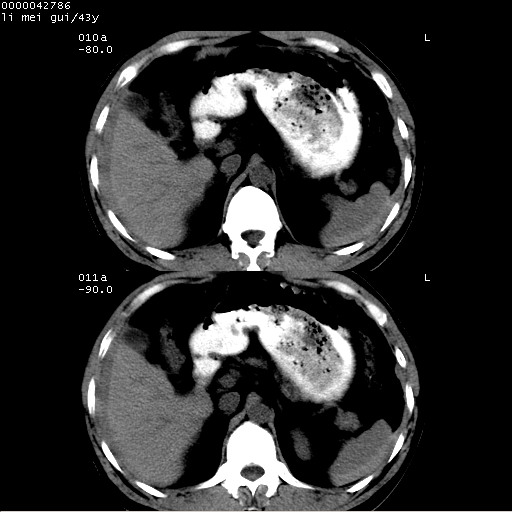

| 患者,男,43岁。突发腹痛2小时,面色苍白,难以平卧。自述近期无明确外伤史,为摩托车驾驶员。 腹部b超检查:脾脏中上极回声异常,肿瘤待排。 临床诊断:腹痛原因待查。 上中腹部ct轴位平扫+增强扫描(层厚10mm,螺距1.0,重建间隔10mm),图像如下: ![]() ![]() ![]() ![]() ![]() ![]() ![]() ![]() ![]() ![]() ![]() ![]() ![]() ![]() ![]() ![]() ![]() ![]() ![]() ![]() ![]() ![]() ![]() ![]() ![]() ![]() ![]() ![]() ![]() ![]() ![]() ![]() ![]() ![]() ![]() zrs发言:支持脾破裂 wwp发言:支持脾破裂并腹水。 xulianj发言:脾脏肿瘤破裂可能性大 zsl6918发言:不像肿瘤出血,考虑还是与外伤后引起的慢性出血有关 zzyy发言:平扫见肝周及脾周积液,脾内密度不均。脾内肿瘤较少见。还是外伤性脾破裂。 沈丘东方医院发言:脾门区一个不均匀强化病灶与其周液体相连多考虑脾占位破裂出血 yixianman001011发言:脾破裂并腹水是可以肯定的,具体原因多以肿瘤性破裂出血,脾脏淋巴瘤可能性大. 结果: 术后,经详细询问患者,其仔细回忆:一月前骑摩托时左侧腰部与别人有“轻微”触碰,因责任在自已,当时又无明显不适,未引起注意。 临床术后诊断:脾破裂并失血性休克(1.外伤性迟发性脾破裂。2.脾脏肿瘤破裂?) 术后标本病检:脾破裂并出血,未见明显肿瘤成份。 原贴地址:http://www.radinet.com.cn/forum_view.asp?forum_id=4&view_id=34070 |